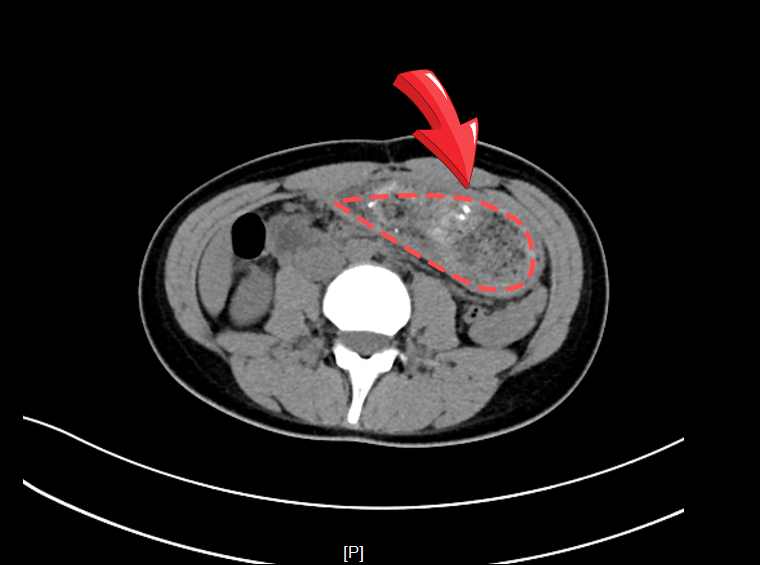

此前同事交班提示,小李的 CT 检查显示胃内存在较多内容物,疑似胃结石,需通过胃镜进一步确诊。

而胃镜检查的结果让在场医护人员深感意外——小李的胃腔几乎被一团缠绕成团的毛发完全占据,毛发与食物残渣牢牢纠缠,形成了巨大的“毛发结石”,如同一只被困在胃中的“黑色野兽”。

▲术前CT及胃镜显示胃内大块毛发团块,几乎占据整个胃腔。